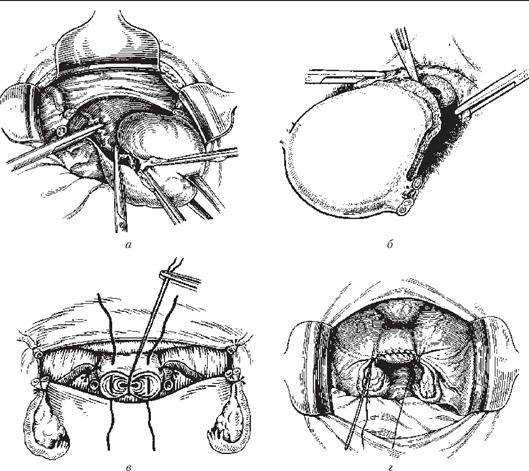

Современные методы лапаротомии и миомэктомии